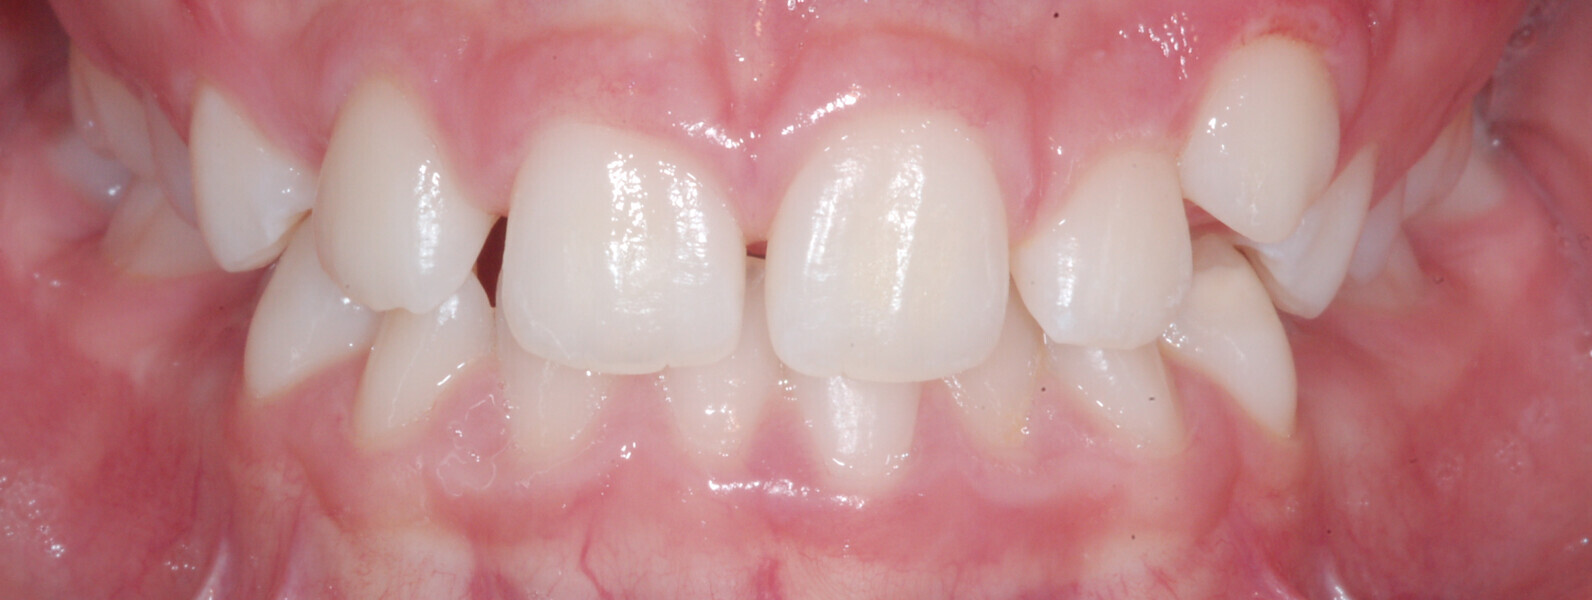

A 14-year-old female patient presented with the chief complaint of midline deviation and dental crowding in both arches. Facial analysis showed a hypodivergent growth pattern, a normal nasolabial angle, a harmonious profile and proper chin projection. Clinical examination revealed a Class III skeletal relationship (ANB = 0°) and Class I molar relationship. The maxillary right canine was absent, and this had led to space loss and mesial drift of posterior teeth on the right side, resulting in a slight Class II molar relationship. The maxillary left canine had erupted in a high position. The mandibular arch displayed crowding despite the agenesis of the right second premolar and the persistence of the primary molar (Figs. 3–11). The radiograph showed the probably premature loss of the maxillary right primary canine and consequently impacted maxillary right permanent canine, and the agenesis of the mandibular right second premolar and the mandibular right third molar (Fig. 12).

Fig. 3